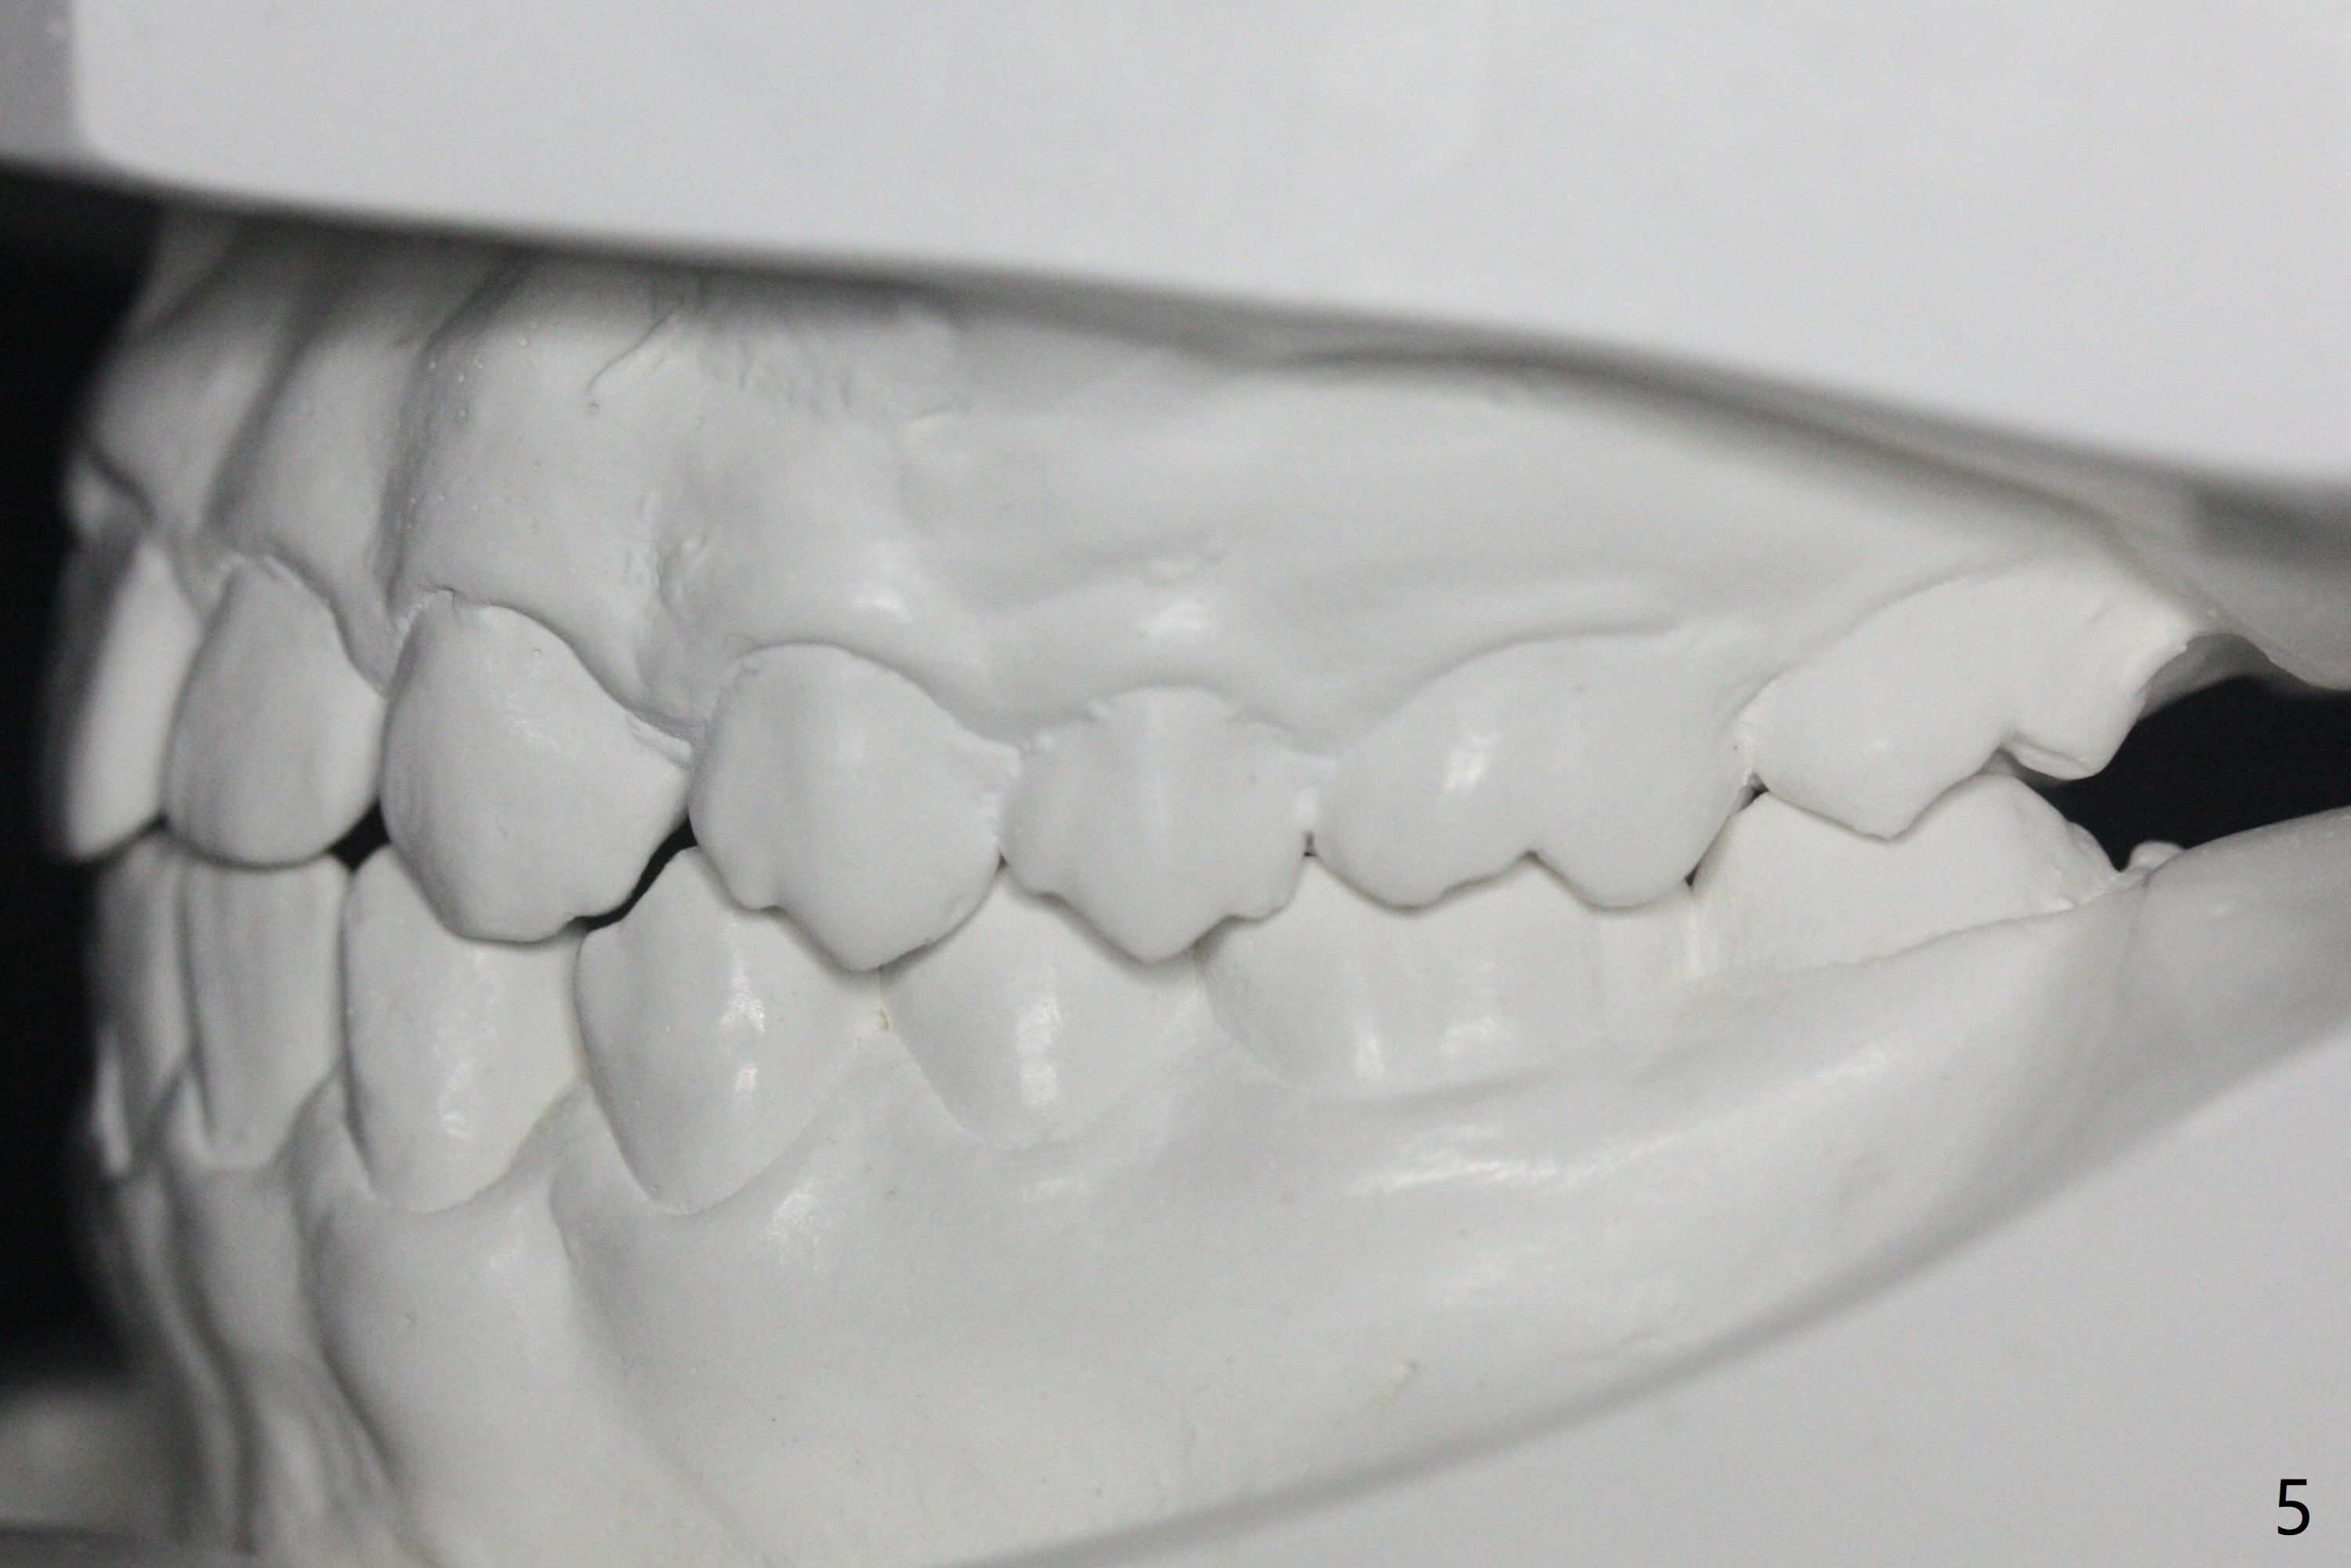

A 15-year-old man finishes orthodontic treatment for congenital missing lateral in 13 months. Molar Class I relationship remains the same (Fig.1,2,4,5). The upper diastemata mesial to 4s (Fig.4,7") close with correction of the upper midline deviation (Fig.2'-4'). The kid is unpleased with the elongated UR1 (Fig.2',3'). In fact it is a preexisting condition (Fig.2 arrow, 2"), but bracket placement at UR1 should have been overcorrected (incisal placement, Fig.3"). The intrusion should be done (Fig.4") before closure of the diastemata, since anchorage may be weakened when the separation between UR1 and 3 increases by using open coil spring. To prevent immediate relapse of the diastema between the upper central incisors, a fixed retainer is placed lingual before debracketing (Fig.6,6',6").